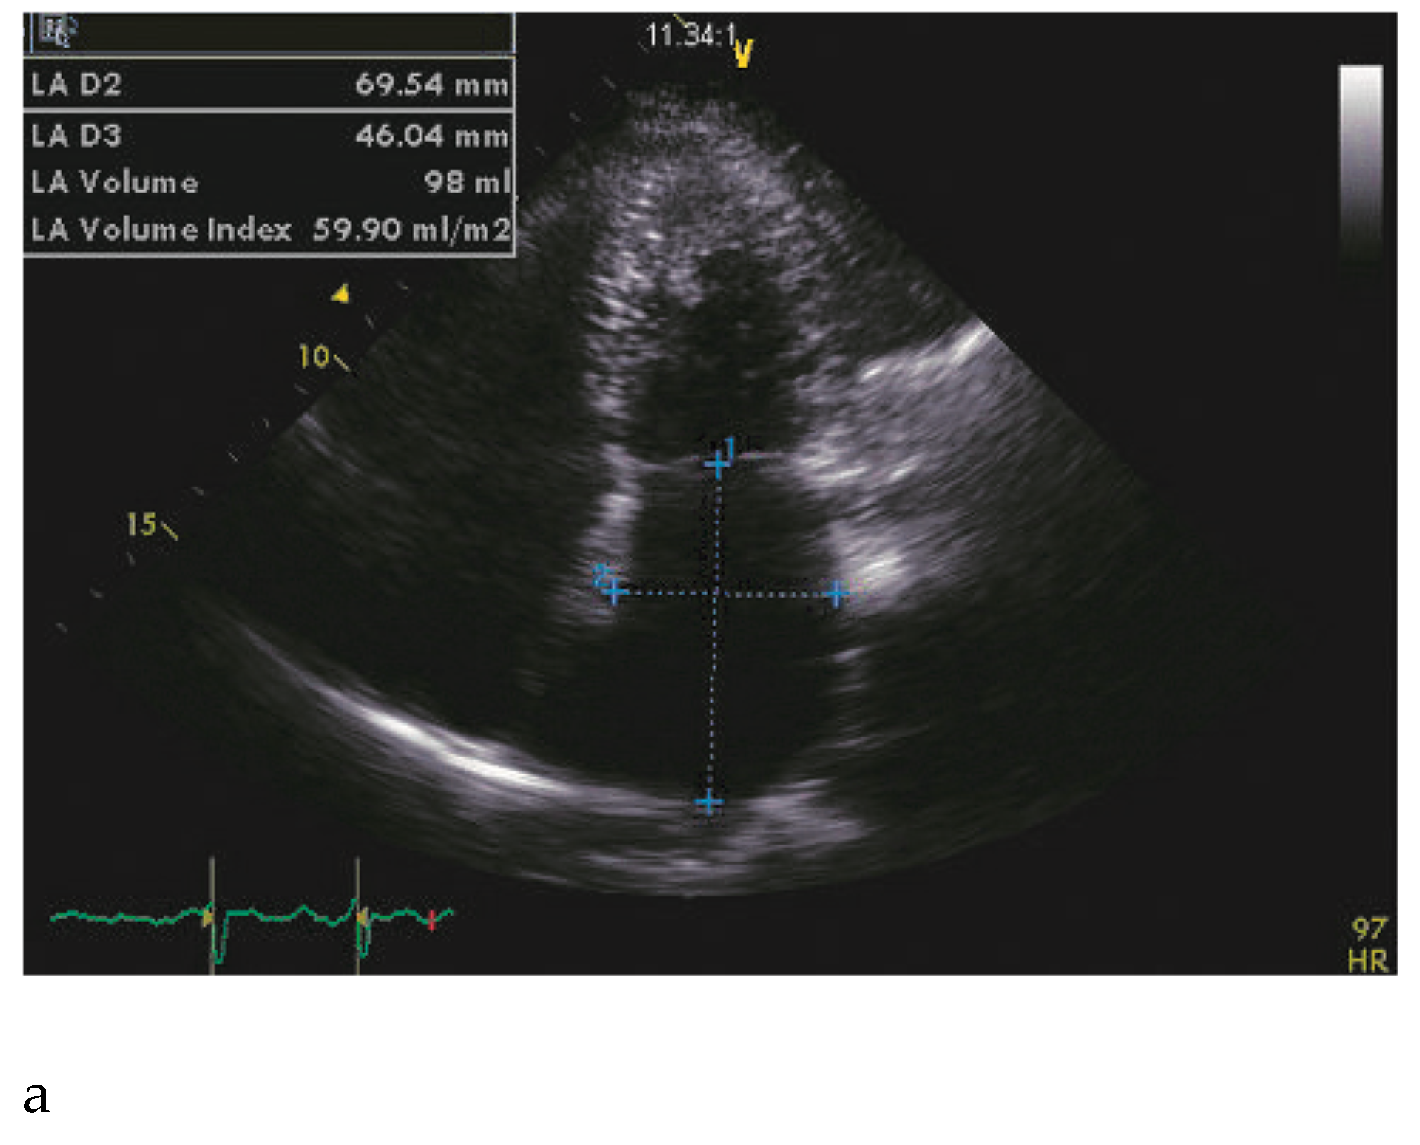

A 66-year-old woman with a family history of hypertrophic cardiomyopathy (HCM) presented with severeprogressive exertional dyspnoea. She had recently complained of palpitations corresponding to atrial fibrillation on the ECG. A transthoracic echocardiogram (TTE) showed nonobstructive, slightly asymmetrical left ventricular hypertrophy (septum and posterior wall thickness respectively measured at 20 and 15 mm). Left ventricular (LV) cavity and ejection fraction (70%) were normal, but both atria were enlarged (Figure 1A). Diastolic function assessment was suggestive of restrictive physiology (Figure 1B). The patient did not improve despite successful cardioversion and intensive medical therapy with maximally-tolerated doses of beta-blockers and verapamil. She was then referred to the catheterisation laboratory to undergo left and right heart catheterisation and coronary angiography after proach) and left heart catheterisations were performed and revealed signs of restrictive physiology without intraventricular dynamic obstruction (Figure 2, Table 1). However, the PA pressure was only mildly elevated and the ventricular diastolic pressure showed a subtle dipplateau pattern (square root sign).

Figure 1. A: Four-chamber view showing a severely dilated left atrium. B: Deceleration time <150 m/sec (in atrial fibrillation), suggestive of a restrictive physiology.